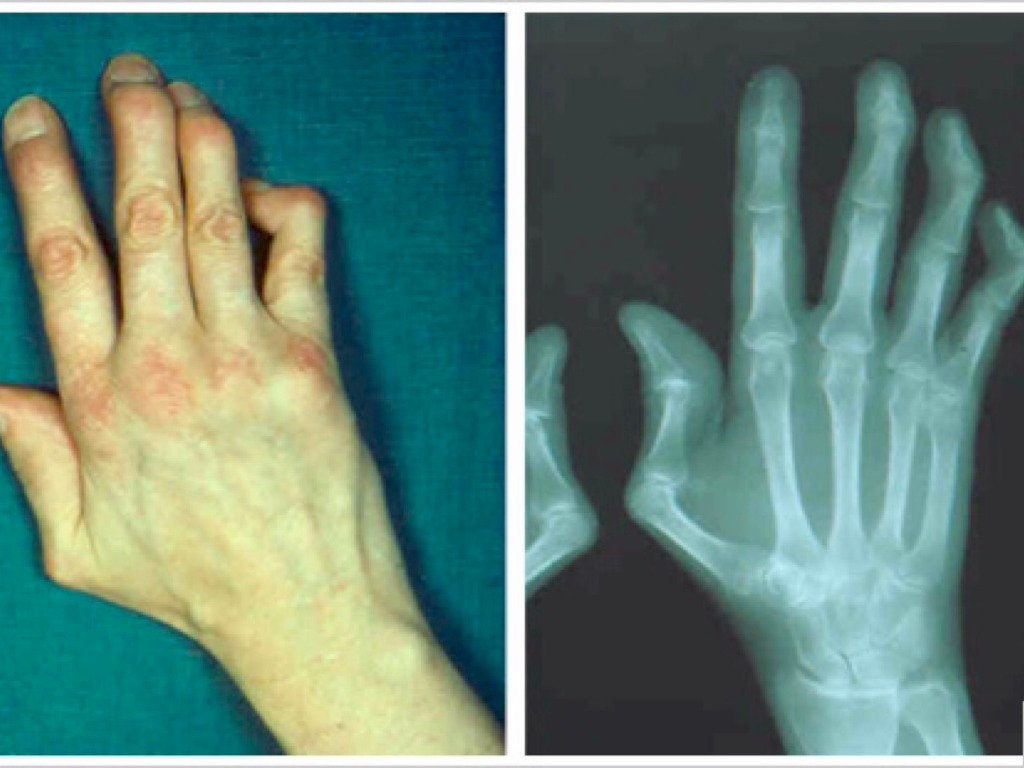

THE PAINFUL EFFECTS OF LUPUS

95% OF PEOPLE DEVELOP WITH SORES AND LESIONS

PAINFUL EFFECTS